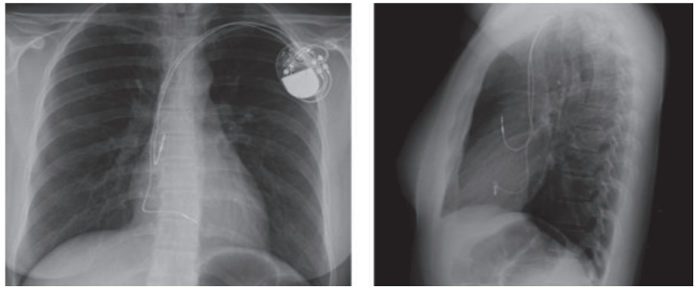

Uma paciente de 68 anos com doença do nódulo sinusal e síncope foi submetida a implante de marcapasso definitivo. De acordo com a sua radiografia de tórax, assinale a opção que representa o tipo de dispositivo implantado.

Marcapasso DDD.